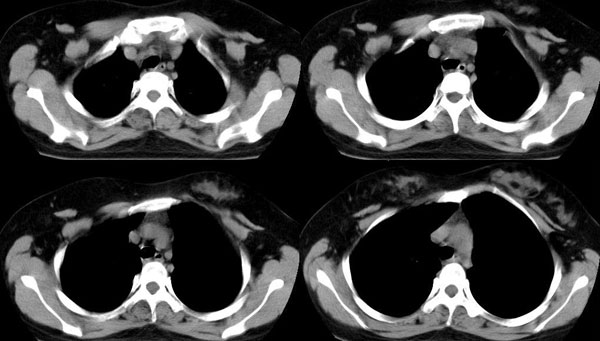

女,22岁,无明显症状

强化

后纵隔食管右侧可见一囊性病灶,密度均匀,边缘光滑,未见钙化,与食管关系密切。无明显强化。

考虑食管囊肿。

鉴别:1、支气管囊肿,多位于气管或气管分叉前后。

2、神经源性肿瘤,实质性肿块,可压迫、侵蚀邻近骨质。

首先定位在肺内。肿块最大径在右下肺叶后基底段,胸椎椎体右边偏后部。与气管、食管无关,如果是支气管或食管囊肿应该有细蒂与之连接。肿块边缘光整、密度均匀一致、轻度均匀强化。右主支气管轻度受压,右肺含气量降低,右胸腔略萎陷。